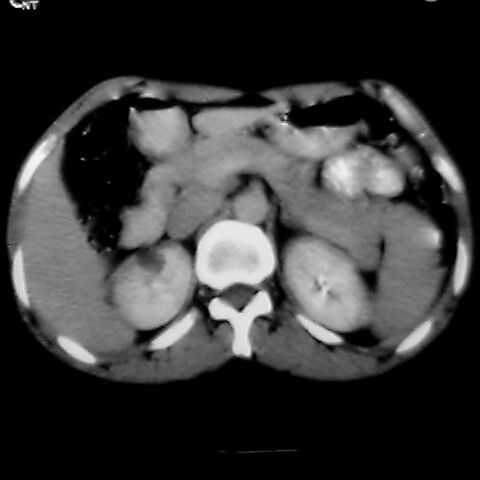

女 48岁 食道癌术前体检发现脾占位。

脾胀内部巨大低密度肿块,边界清或不清,中心坏死,轻度增强,内见散在钙化,结合食道癌病史多考虑:转移癌.

脾脏低密度灶伴钙化,增强化明显,中心见液化坏死灶,强化延时明显。考虑血管瘤。转移瘤待排。

1肝右下叶小囊肿2右肾上极囊肿或错构瘤3脾脏不典型血管瘤可能性大.

1,脾血管瘤。2,右肝,右肾小囊肿。